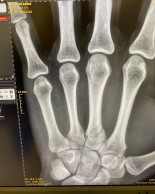

Jolanda Neff anuncia que sufre una fractura en su mano

Ahora ella misma anuncia que en la caída se ha fracturado la mano izquierda y en su publicación de redes sociales se pueden apreciar los rasguños y heridas que tiene por todo el cuerpo.